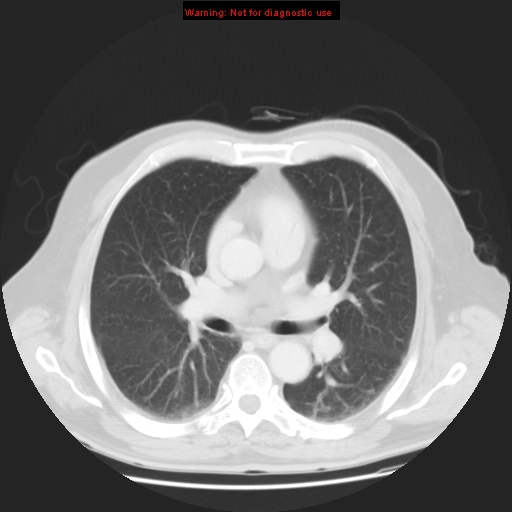

Bệnh phổi do xạ trị (Radiation-induced lung disease - RILD)

Bệnh phổi do thuốc (Drug-induced lung disease)